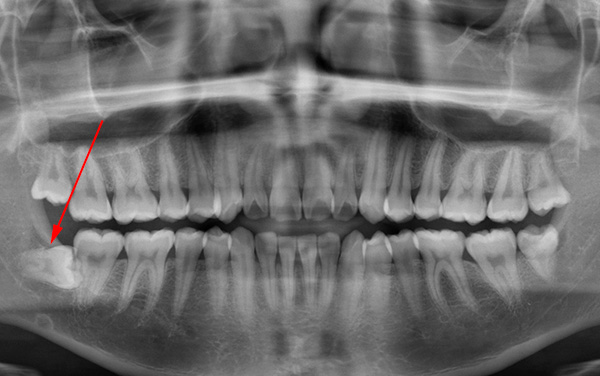

Il seguente è un esempio di un dente del giudizio orizzontale nella mascella: